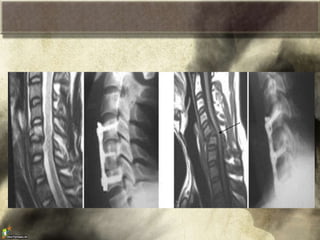

Criterios de Inestabilidad de la

Columna Cervical (White y Punjavi)

• Angulación mayor

de 11 grados entre

espacios

intervertebrales

• Listesis mayor de

3 mm

Criterios de Inestabilidadde la Columna Cervical (White y Punjavi) • Angulación mayor de 11 grados entre espacios intervertebrales • Listesis mayor de 3 mm